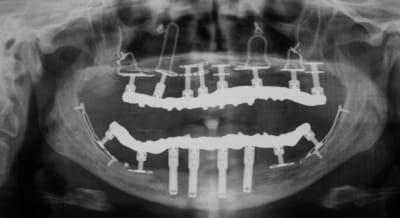

c'est du juxta osseux ca?

pas du juxta osseux ,ignare, des implants à plaque!

j'aimerais qu'on m'explique ce qu'on voit sur la pano précisément,

c'et spas ironique, c'ets juste pour savoir un truc.

Merci beaucoup.

> j'aimerais qu'on m'explique ce qu'on voit sur la pano précisément,

> c'et spas ironique, c'ets juste pour savoir un truc.

> Merci beaucoup.

bon, j't'explique

en haut c'est ula-up barbimplant

(et barbosdur et barbicrête et barbalatérale et barbalalaaaaa)

L'oeil averti remarquera la présence d'un type d'implant particulier, les implants à plaque. Ces implants permettent d'équiper des patients qui ne pouvaient pas être traités jusqu'à ce jour. Ces implants ne sont pas encore recouverts d'os, les radiographies ayant été prises juste après la chirurgie implantaire. Mais nous savons qu'une fois équipé par ces implants, l'os va se régénérer et même croître sous la fonction.

Il est inutile de chercher ces implants dans un catalogue du commerce implantaire, ils sont, pour l'instant, uniquement disponibles pour les praticiens qui ont montré leur dextérité lors de leur formation en implantologie basale.